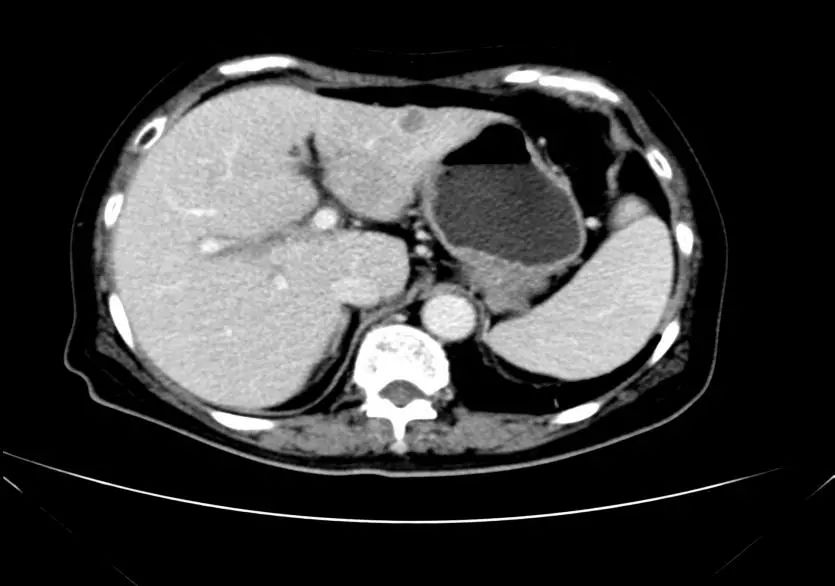

• CT示:肝转移

CT-T

CT-H1

影像学检查结果评估:cPD。